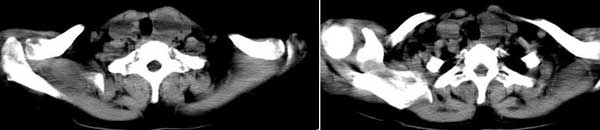

女 48岁 无意中发现左侧颈部肿块

左侧甲状腺下极可见类圆形结节样低密度病灶,边缘清晰,未见明显周围组织受侵,颈部未见明确淋巴结肿大;右侧甲状腺形态密度未见异常。

诊断意见:左侧甲状腺结节样病灶,多考虑甲状腺腺瘤。建议ect检查。

见双侧结节,边清。1甲状腺肿,2腺瘤。

双侧甲状腺弥漫性密度减低,左侧可见低密度结节边界清晰,周围软组织未见异常,考虑双侧结节性甲状腺肿